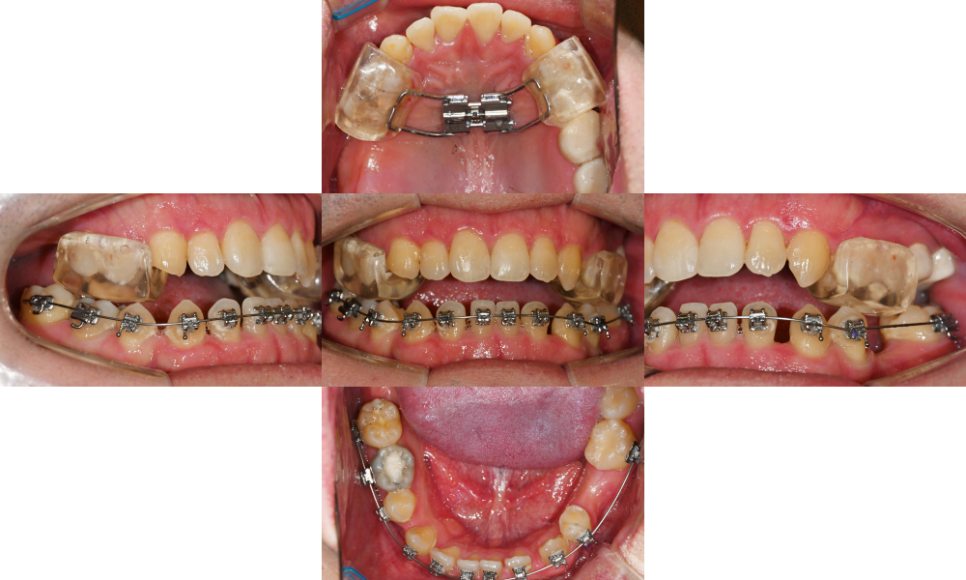

24.01.10

치아 결손 부위에

임플란트를 식립하기 전에

교정 치료를 먼저 진행하는 경우가 많습니다.

이는 치아 배열을 정리한 후

임플란트를 적절한 위치에

식립하기 위함이에요.

24.08.19//25.01.13

교정 치료 과정에서

반대교합을 동시에 개선하면서

임플란트 식립을 위한 공간을

확보하게 됩니다.

필요에 따라 치간이개를 조절하고

전체적인 치아 배열을 정리해요.